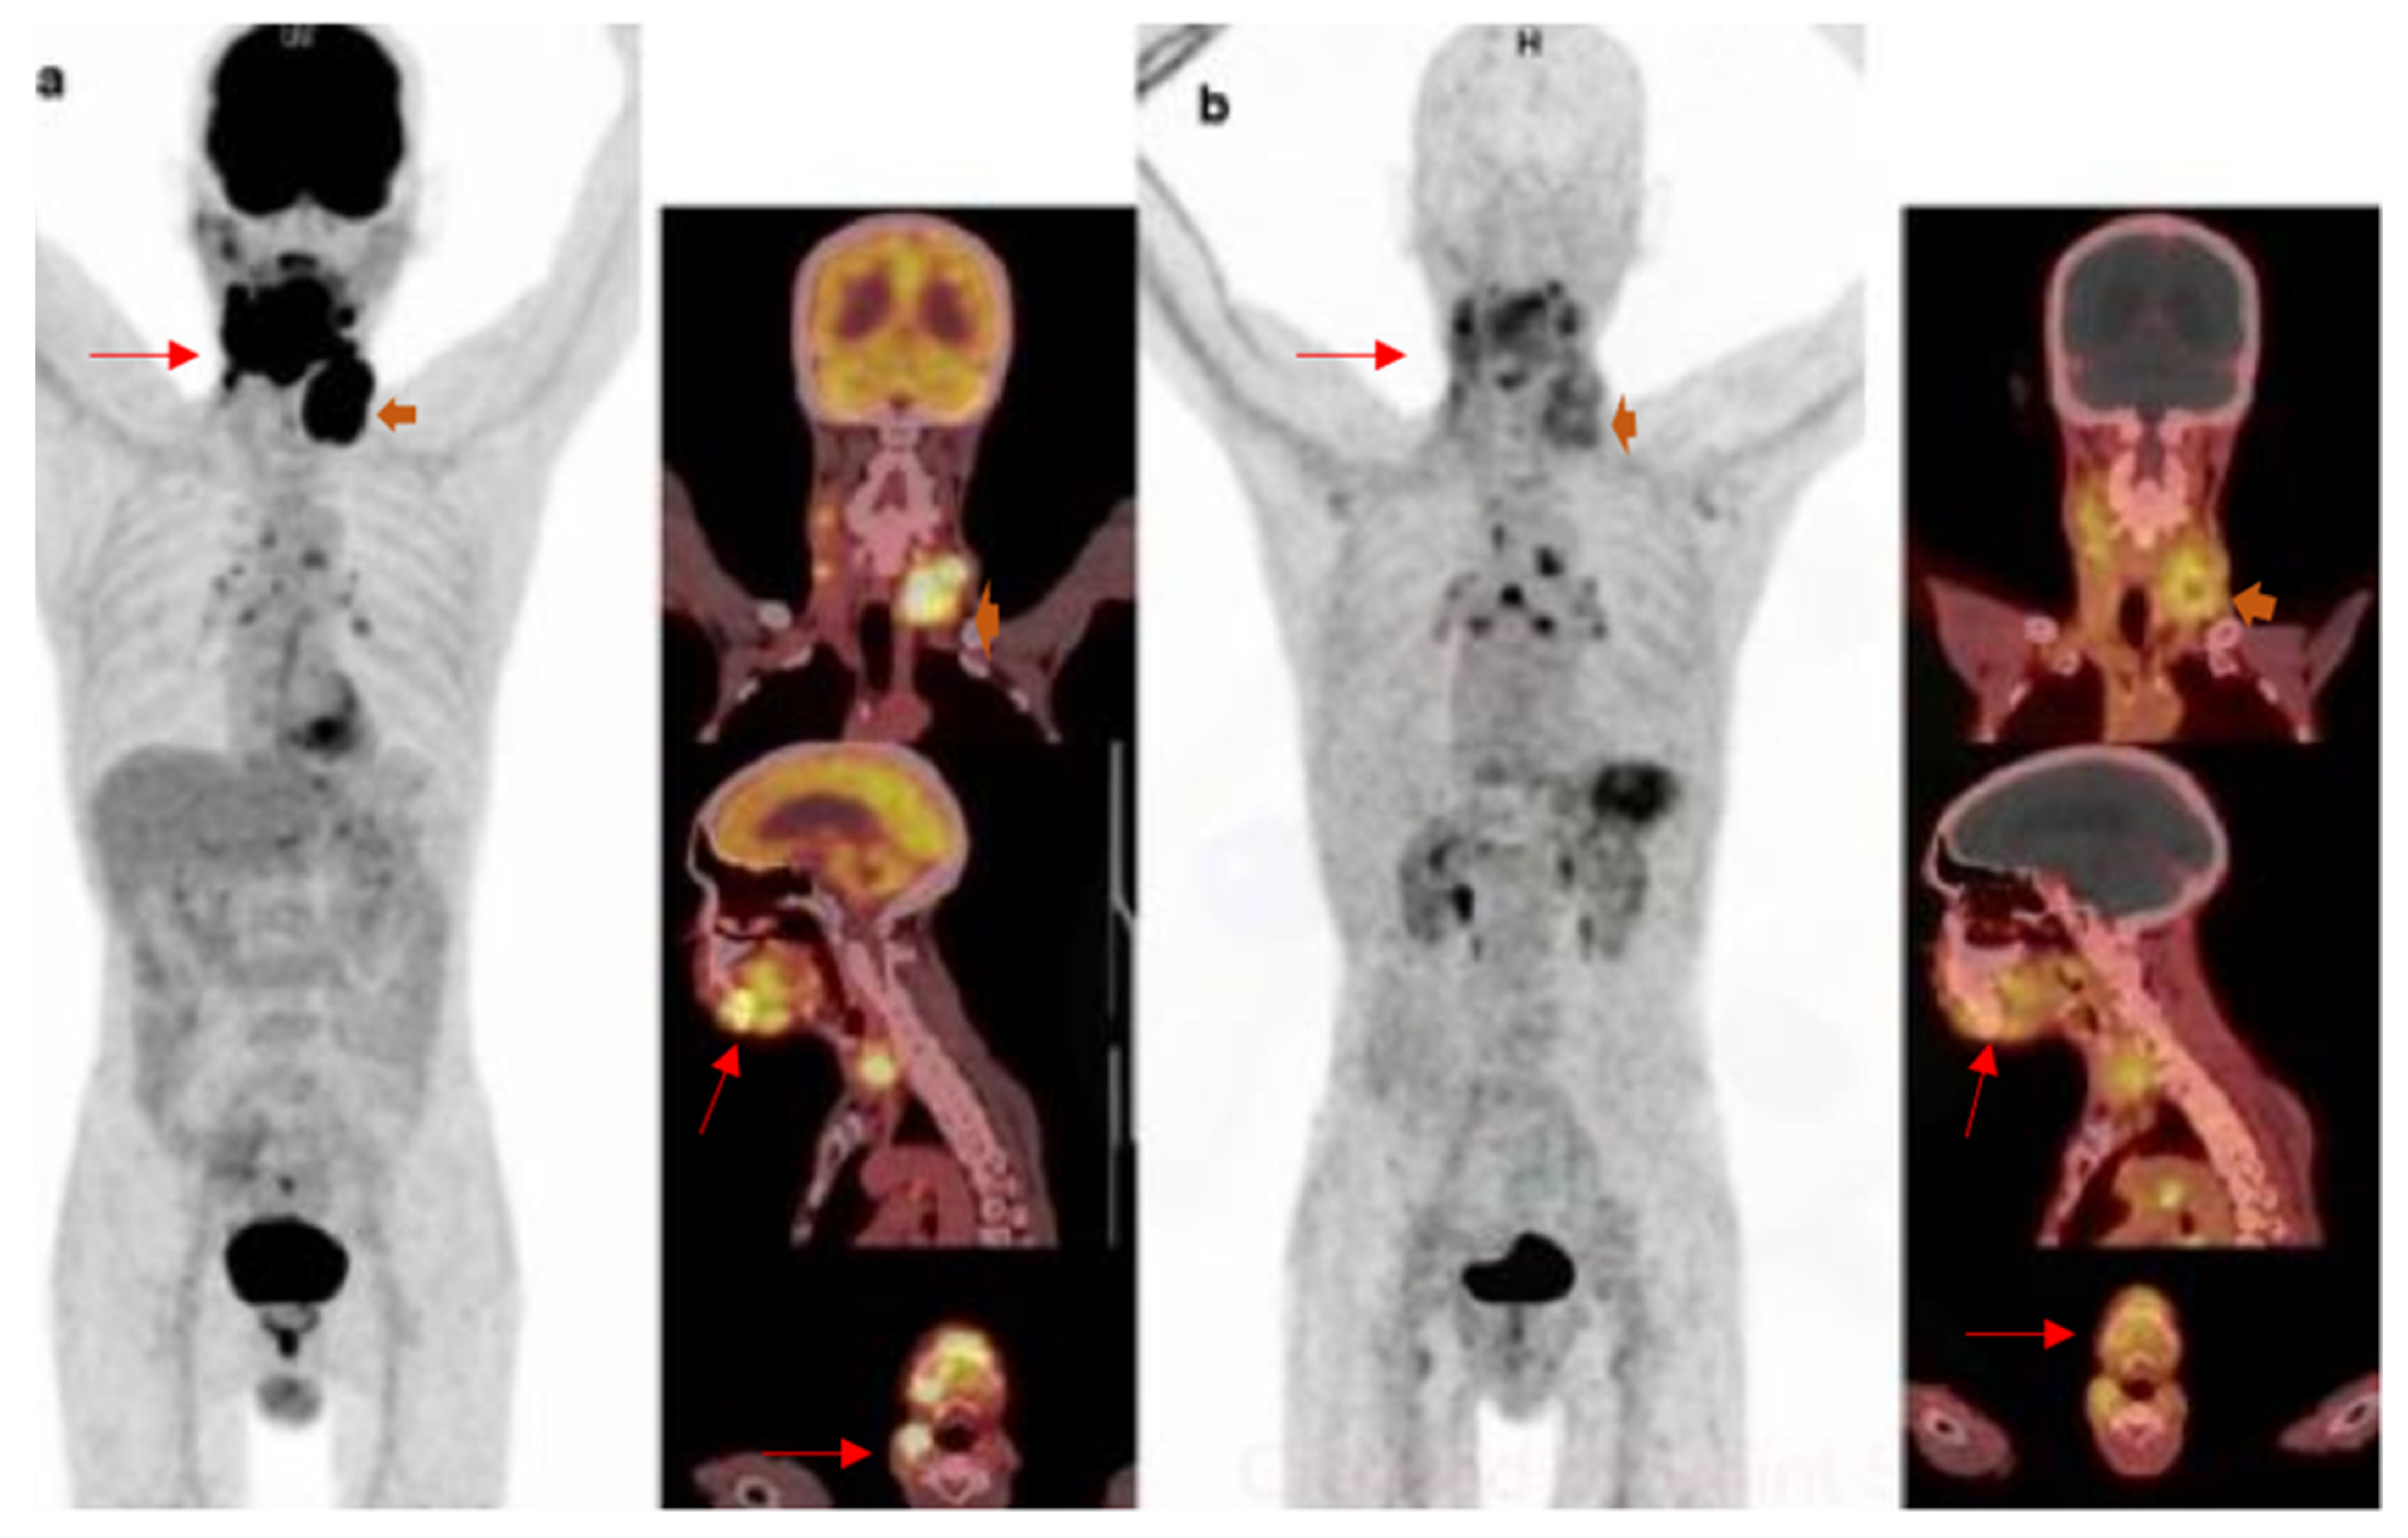

- Linde, P.; Baues, C.; Wegen, S.; Trommer, M.; Quaas, A.; Rosenbrock, J.; Celik, E.; Marnitz, S.; Bruns, C.J.; Fischer, T.; et al. Pentixafor PET/CT for imaging of chemokine receptor 4 expression in esophageal cancer—A first clinical approach. Cancer Imaging 2021, 21, 22. [Google Scholar] [CrossRef]

- Werner, R.A.; Kircher, S.; Higuchi, T.; Kircher, M.; Schirbel, A.; Wester, H.J.; Buck, A.K.; Pomper, M.G.; Rowe, S.P.; Lapa, C. CXCR4-Directed Imaging in Solid Tumors. Front. Oncol. 2019, 9, 770. [Google Scholar] [CrossRef]